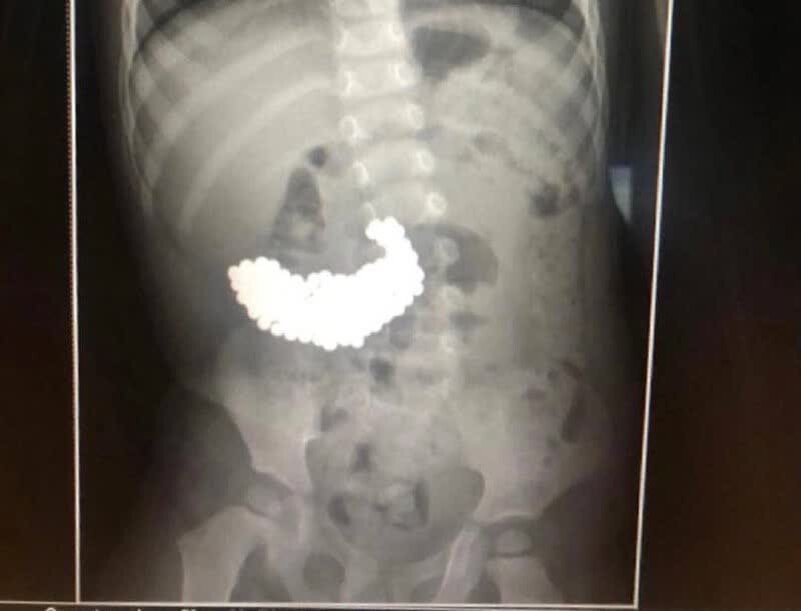

Московские врачи спасли двухлетнего мальчика, вытащив из его желудка 209 магнитных шариков.

Сложно сказать, почему малыш наелся магнитов, но желудок уже начал их переваривать, появились кровотечения. Это заметили родители и обратились за помощью

Медики поняли, что они всё ещё в желудке. Значит, можно обойтись без разрезов и вытащить эндоскопическим методом. Но выяснилось что у шариков острые края

Медики поняли, что они всё ещё в желудке. Значит, можно обойтись без разрезов и вытащить эндоскопическим методом. Но выяснилось что у шариков острые края (из-за желудочного сока) могли порезать слизистую и примагнититься к эндоскопу. В итоге операция шла сложно и долго — два часа, но завершилась успешно: мальчишка спасён! Врачи просто молодци